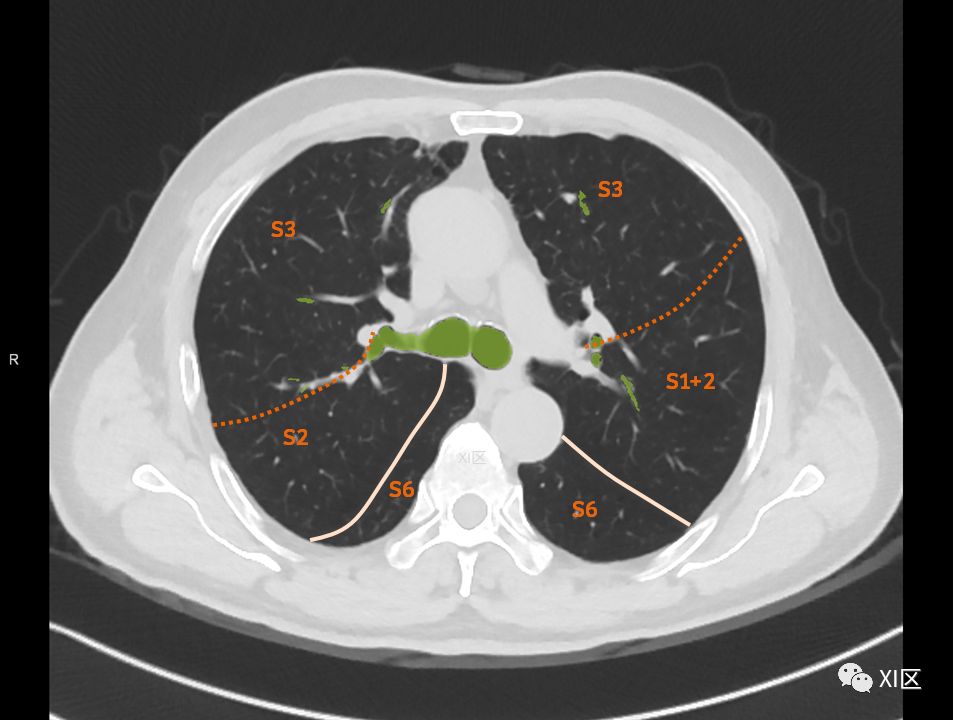

在进行肺的分段时,可以上下观察浏览,沿着相应气管的走形可以更容易准确地进行分段。

肺的分段

肺的断层分段示意图